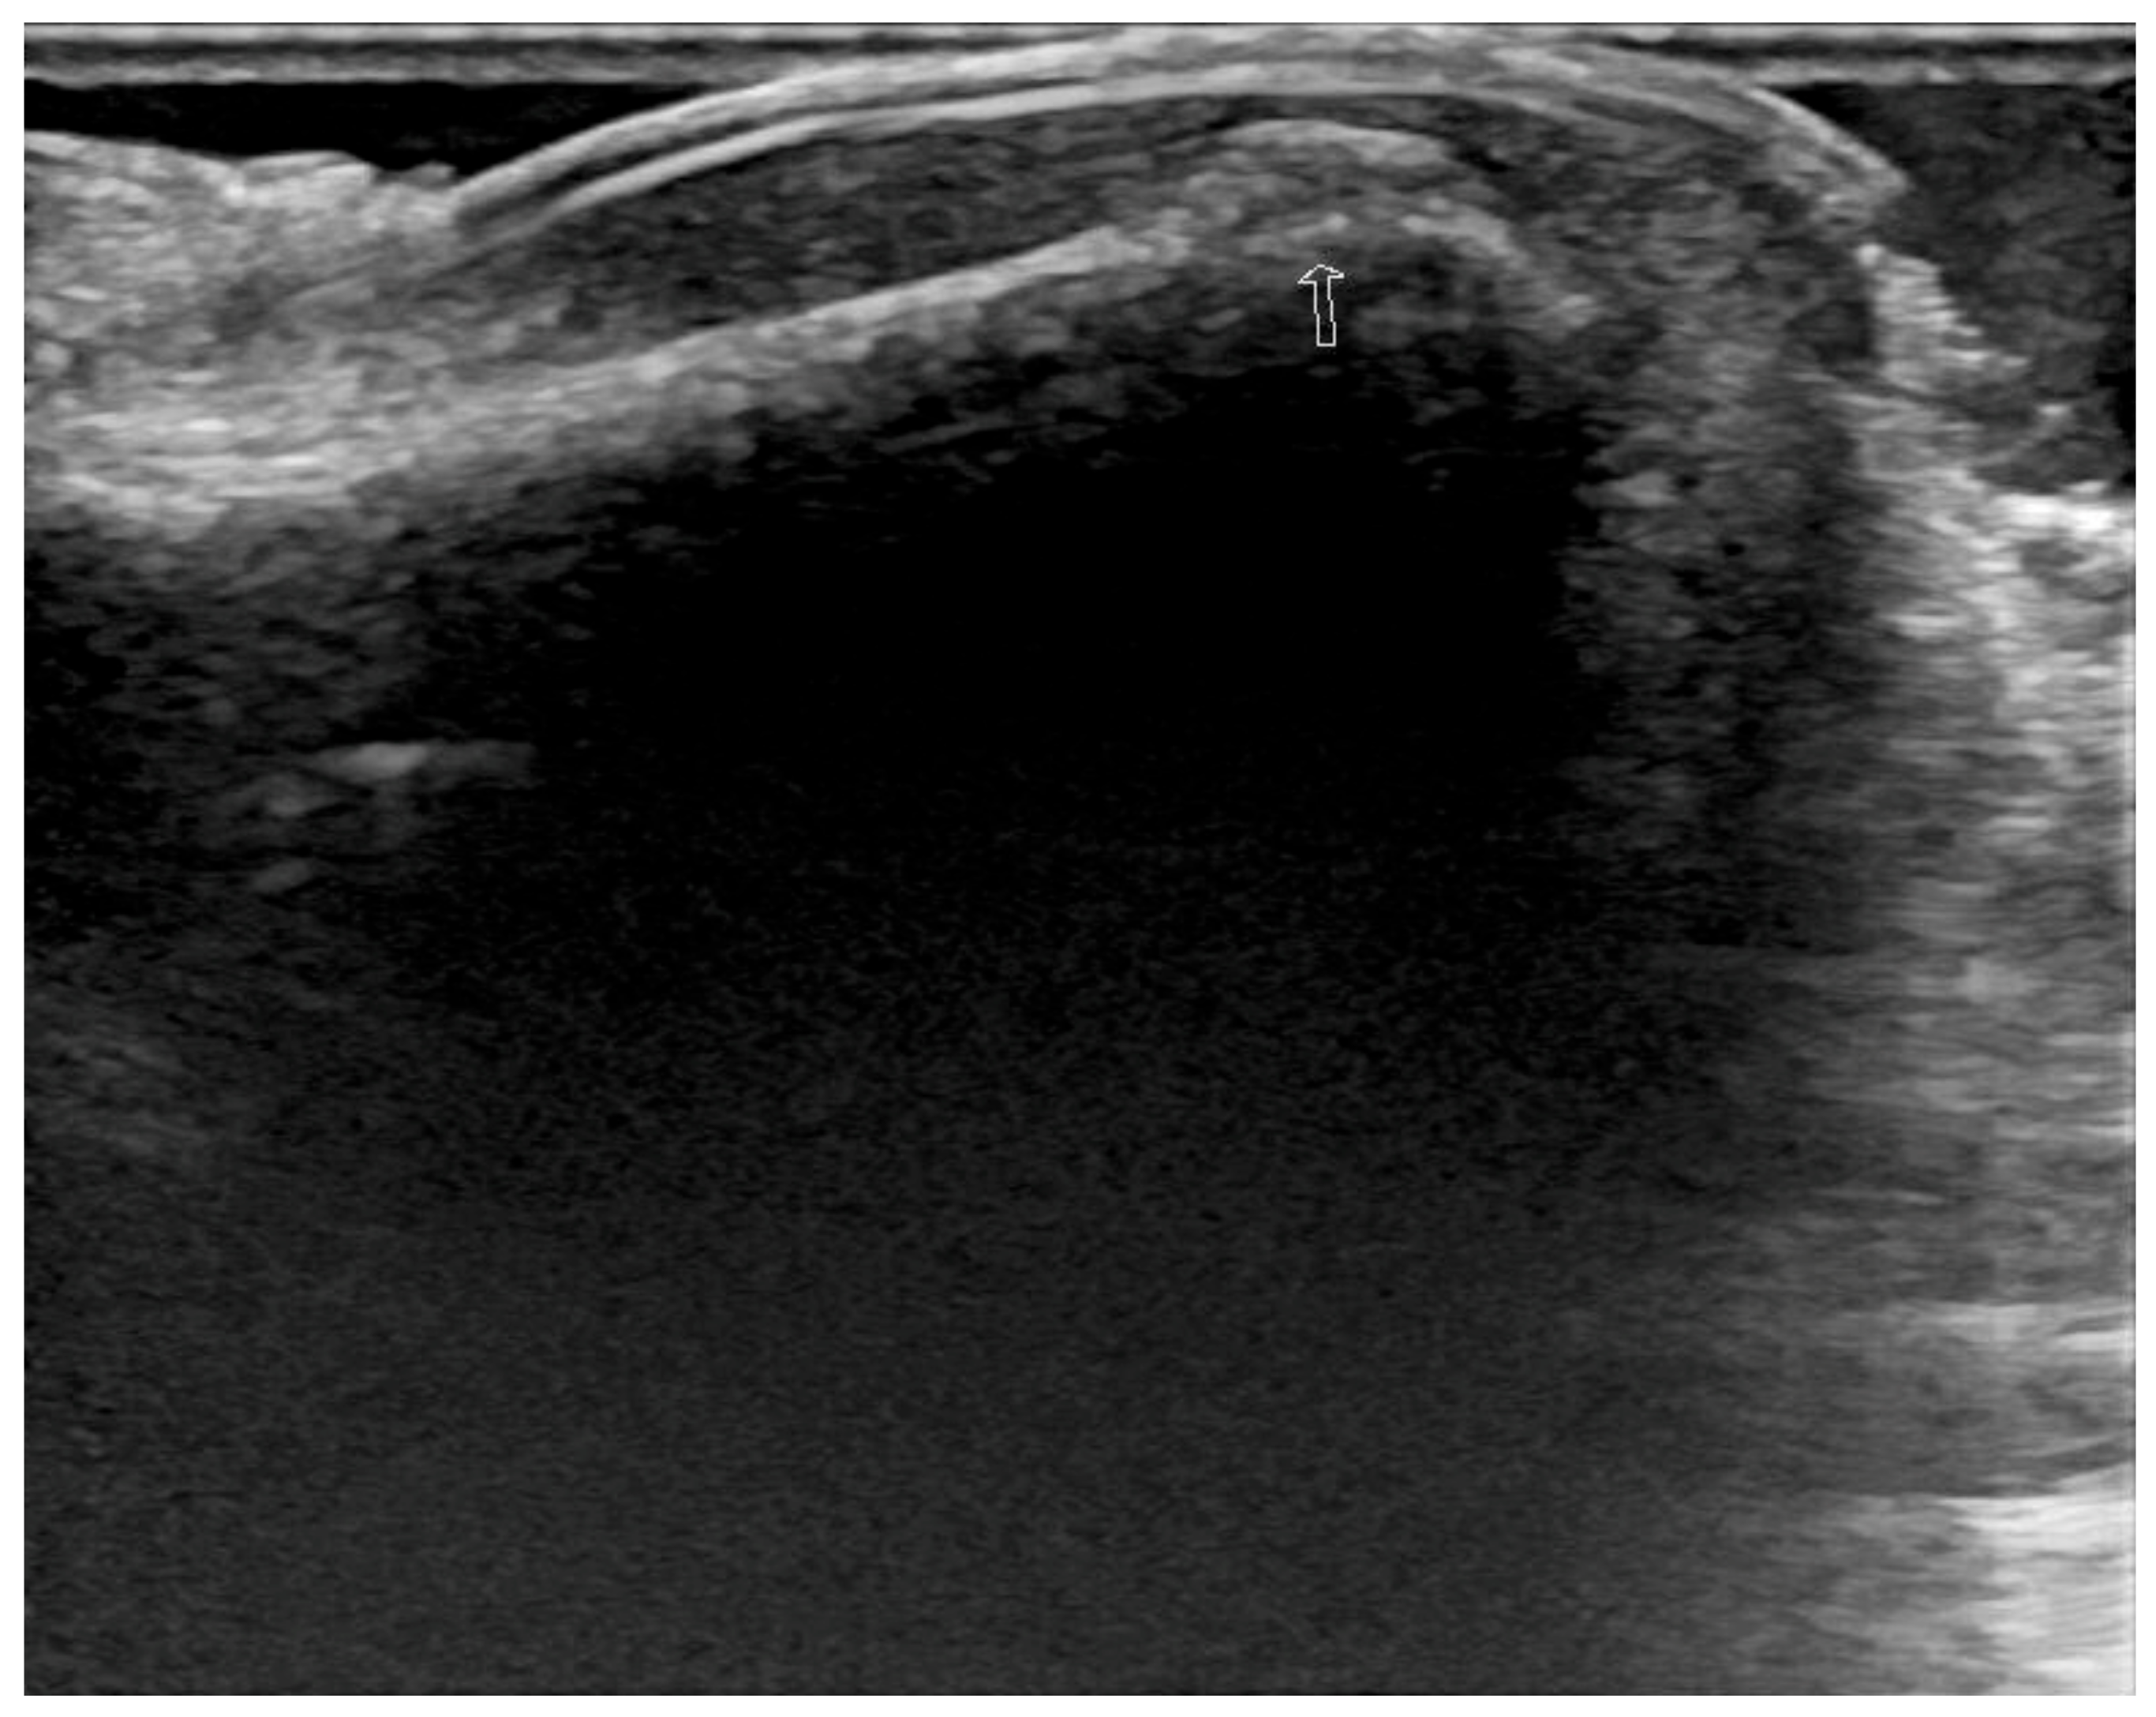

2. Case Report